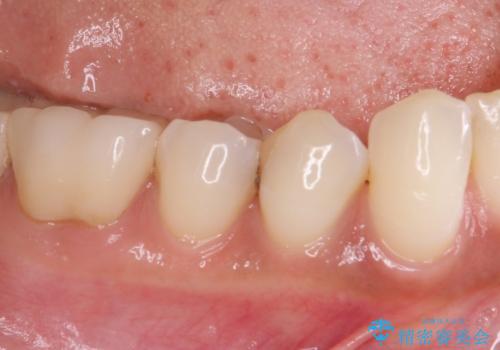

下顎の目立つ位置であるため、セラミックインレーによる修復治療を行うこととしました。

精密に型取りを行ったセラミックインレーを装着したことで、治療後にはしみたり痛んだりという症状は治まりました。